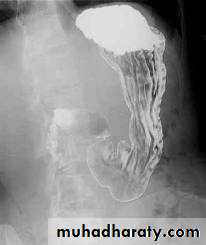

The Normal Anatomy of Stomach1- Shape.2-Size.3-Site.4-Anatomical parts.5-Mucosal pattern.

Normal Anatomy of DuodenumDuodenal cap.Duodenal loop

Barium meal Fluoroscopy + spot films Preparation